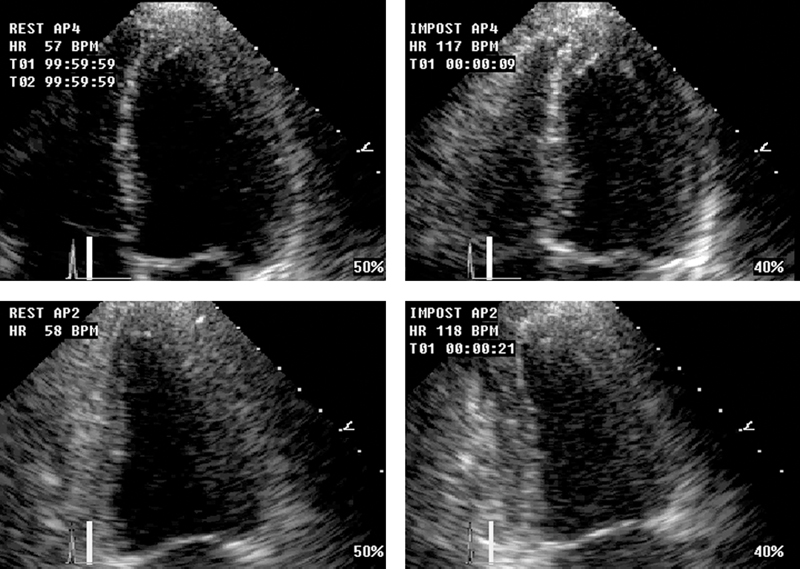

فحوصات تشخيصية لبعض امراض القلب والشرايين التاجية